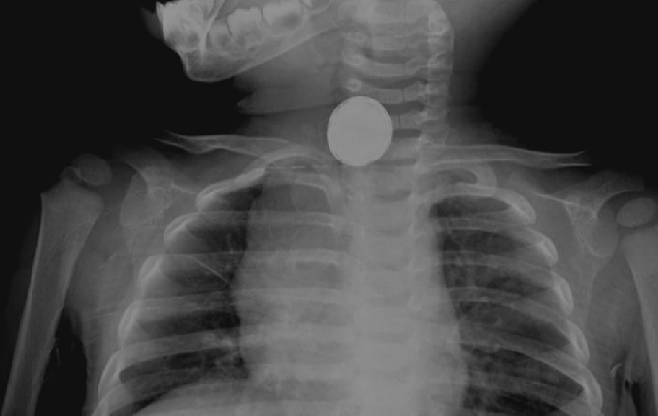

近日,10个月大的株洲宝宝小山(化名),在家玩玩具车时,好奇地将纽扣电池放入嘴中吞下。小山爸爸通过监控发现后,赶紧带孩子来到湖南省儿童医院就诊。近半个月,湖南省儿童医院消化营养科共收治了14例,开展了8台内镜下消化道异物取出手术。取出的异物包括硬币、回形针、棒棒糖棍子、磁力珠、纽扣电池等。 湖南省儿童医院消化营养科副主任、主任医师赵红梅提醒,幼儿对周围事物充满好奇,喜欢将小物品放入口中,家长要加强对孩子的保护,一旦发现孩子吞咽异物,应立即停止一切活动,保持冷静。 “电池滞留在同一个地方,如果超过12小时,肯定会造成腐蚀和穿孔。”赵红梅介绍,由于小山没有出现任何不适,而且体内电池位置不断变化,判断自行排出的可能性较大,所以先行住院观察。 异物卡顿在消化道的不同部位,会导致各种不同的表现。比如异物在胃内或者肠道内时,大多没有明显的不适表现;而当异物卡在口咽部、食管内时,患者不适症状较明显,可表现为咽喉疼痛、口水增多,甚至带血,有异物阻塞感、吞咽困难,并可出现恶心、呕吐、咳嗽、气促等症状。年幼的儿童、精神疾病患者发生消化道异物时,往往不能详细描述不适症状,通过观察体征,可发现其拒食、流口水、唾液带血、呕吐、呼吸困难、气喘、出现过激的情绪动作等异常表现。 异物进入消化道存在多重风险。尖锐或硬质的异物(如鱼刺、鸡骨头、玻璃碎片)可能划伤或穿透消化道黏膜,引起口腔、咽喉、食管、胃或肠道的损伤。严重的穿透伤可能导致器官穿孔,进而引发腹膜炎等危及生命的并发症,甚至需要外科手术的干预。 较大或难以消化的异物(如硬币、玩具小部件)可能堵塞食管或肠道,阻碍正常消化功能,引起剧烈的腹部疼痛、呕吐等症状,长时间的阻塞还可能导致肠壁缺血、坏死乃至穿孔。 异物滞留在体内可能成为细菌滋生的温床,导致局部或全身性感染,特别是当异物造成黏膜损伤时,感染风险进一步增加。长期停留的异物即使不直接造成损伤,也可能引起周围组织的慢性炎症反应,形成肉芽肿,影响消化道的功能和结构完整性。 同时,对于儿童,经历消化道异物事件可能留下心理阴影,出现厌食、惧怕进食等问题,影响正常的成长发育。 消化道异物如何预防?第一,关注孩子所处环境的环境安全。定期检查家中的小件物品,如纽扣电池、硬币、小玩具零件等,确保它们存放在儿童无法触及的地方,避免儿童碰撞后误吞脱落的小零件。所有药物都应放置在高处且带锁的橱柜内,避免儿童误食。 第二,重视孩子的饮食安全。确保儿童的食物被切割成易于咀嚼的小块,避免整颗坚果等圆形水果未经切割就被吞咽。幼儿吃饭时应有大人陪同,避免边玩边吃,确保食物充分咀嚼再吞咽。尽量避免让儿童食用含有骨刺、果核的食物,以及未煮熟的蔬菜和肉类。 第三,培养孩子良好的生活习惯。从小教导儿童不要将任何非食物放入嘴里,强化“不是吃的不能放进嘴里”的安全观念。父母及照顾者应作为榜样,不在儿童面前随意将非食物物品放入口中,例如笔帽、钥匙等。 第四,在给孩子买玩具玩游戏时,注意游戏安全。购买玩具时,选择符合年龄段的安全玩具,避免有可拆卸小部件的玩具。当儿童玩弄小物件或拼图类玩具时,应在成人视线范围内,随时提醒和纠正不当行为。 第五,家长及时做好应急预案。家长应该学会基本的急救技能,如海姆立克手法,了解异物卡喉的初步处理方法。 |